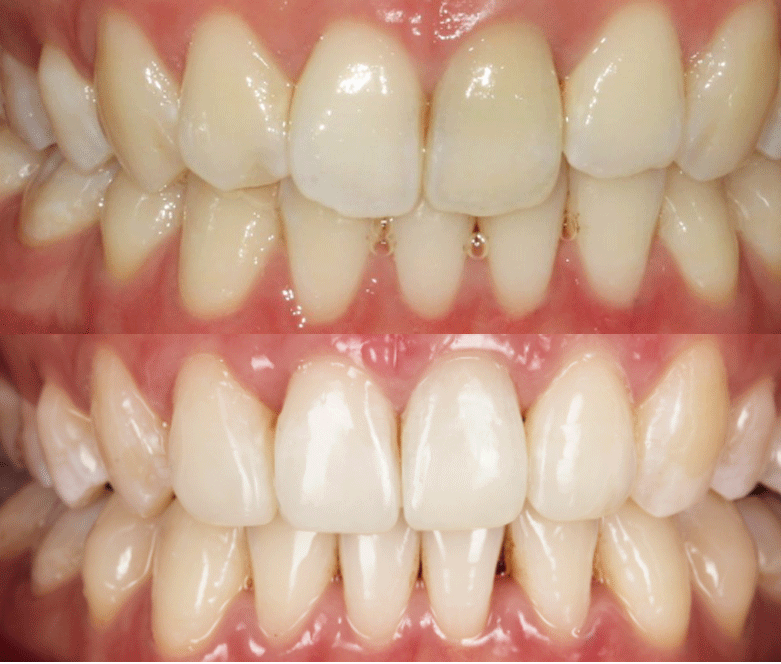

We will then map out a complete treatment plan showing the gradual realignment that will reposition the teeth from their current position to where they will be when the treatment is complete.